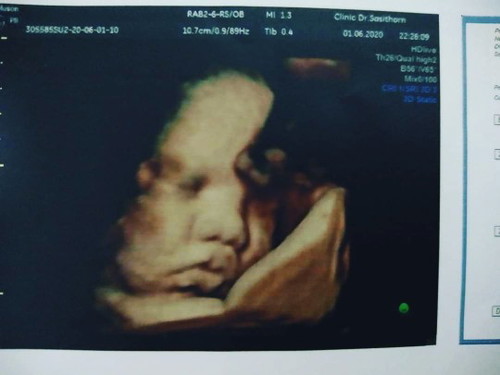

ภาพเหมือนแม่บ้านนี้เลยคะ ซาวตอน33wคะ

นี้คุณแม่ซาวตอนกี่เดือนค่ะ